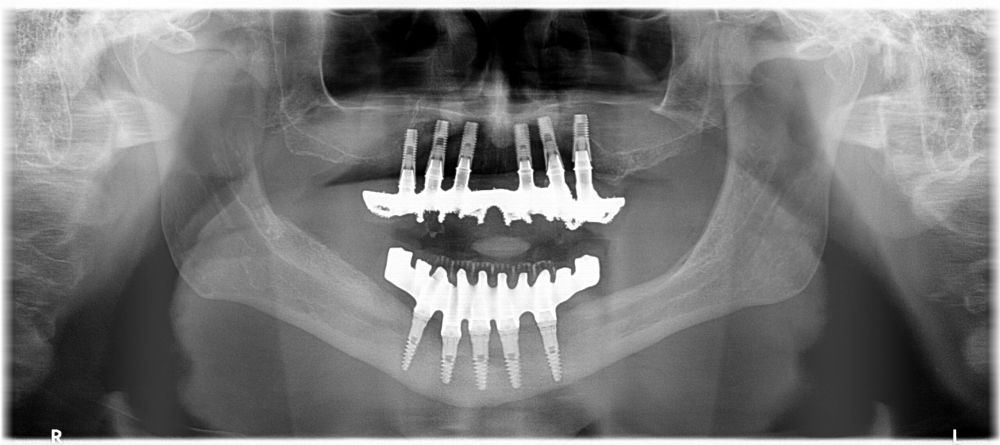

We present the clinical case of a 65-year-old patient with an implant-supported dentoalveolar rehabilitation on implants in the upper arch, placed in 2010, on which he referred pain, mobility and suppuration. After an orthopantomography, we observed a severe generalised perimplantitis in the upper arch, affecting all implants (Figure 1). It was explained to the patient that it was not possible to perform a bone regeneration of the lost tissues.

For this purpose, intraoral photographs were made and the complete prosthesis of the patient was used for the different planning tests. First, the double scanning technique was used, adding different radiopaque markers with gutta percha in the prosthesis10 (Figure 3). Then, the scanning was obtained with a conical beam computerized tomography (CBCT), (Planmeca ProMax 3D, Helsinki, Finland), both the prosthesis and the patient with his prosthesis stabilized with a silicone bite registration (Figure 4). In addition, an intraoral scan of the patient’s prosthesis was performed. From this, a personalized structure was designed subperiosteal sintered in Titanium (Ti-6-4) (Custom 3D®) with 6 Multi-Unit® type connections (Branemark, Nobel Biocare) and fixed with osteosynthesis screws in the higher density and volume areas of the malar bone and upper jaw (Figure 5 and 6). At the same time, with the STL digital test of the planning of the mesh, and with the scanning of our complete prosthesis, the laboratory technician made an implantosupported rehabilitation milled in polymethylmethacrylate (PMMA) with Multi-Unit® type titanium interfaces for immediate loading (figures 7 and 8).

The surgical procedure was performed under general anaesthesia and nasotracheal intubation. A supracrestal incision and detachment of a maxillary flap of total thickness was made (Figures 9 and 10). The boundaries of the dissection were both infraorbital ridges, both laterally malar bodies and the anterior half of the hard palate caudally. In addition, a customized cutting guide was used so that the SI was completely in direct contact with the bone (Figure 11) and the mesh was fixed with the different 1.5 mm osteosynthesis screws in the nasal and zygomatic buttresses (KLS Martin, Freiburg, Germany) (Figure 12). The closure was performed with nonresorbable suture. Finally, the PMMA provisional rehabilitation was screwed for the immediate load, with a torque of 20 N on the implants (Figures 13-15).